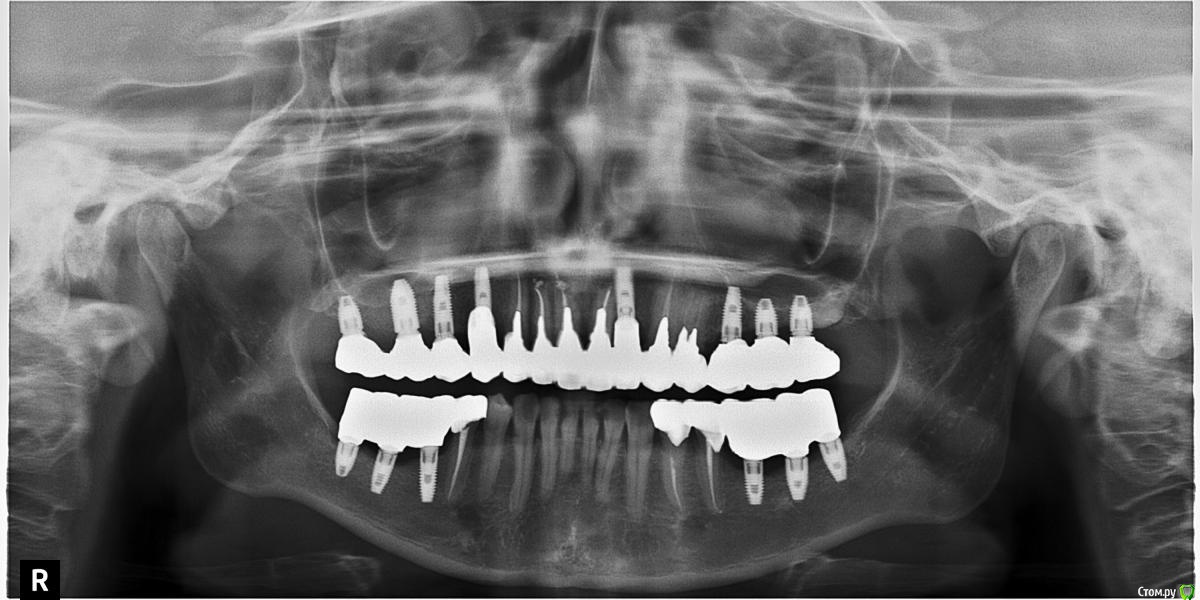

rus-fly Опубликовано 25 сентября, 2018 Поделиться Опубликовано 25 сентября, 2018 Завствуйте. Мне 36 лет. После долгого отсутствия большого количества зубов, мне было проведено тотальное протезирование на имплантатах и частично на своих зубах. Два раза в жевательной зоне переделывали конструкции протезов. После 1го протезирования был дискомфорт, ощущение, что прикус занизили и нижняя челюсть съезжала назад. Переделали, вроде бы этот момент ушел, но на нижней челюсти стала уходить костная ткань и десна, появились пробелы между десной и конструкцией и постоянно воспаленные десны. В июле этого года, опять переделали нижние конструкции, уплотнили соединение. На данный момент, справа болит челюстной сустав. При накусывании больно, щелкает, отдает в ухо. В спокойном состоянии нет смыкания с правой стороны. Когда полностью смыкаю, ощущение напряжения в челюсти с правой стороны. Жую только левой. Прикладываю снимок. Хотелось бы услышать мнение специалистов по моему случаю. И еще вопрос, если прикус выставлен не правильно, видно ли это по снимку? Буду очень благодарна за ответы. Ссылка на комментарий